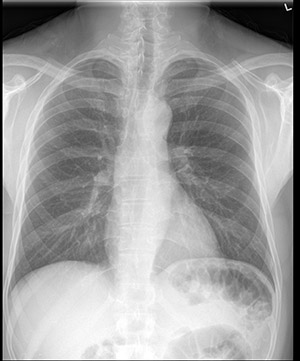

raios x torácicos padrão